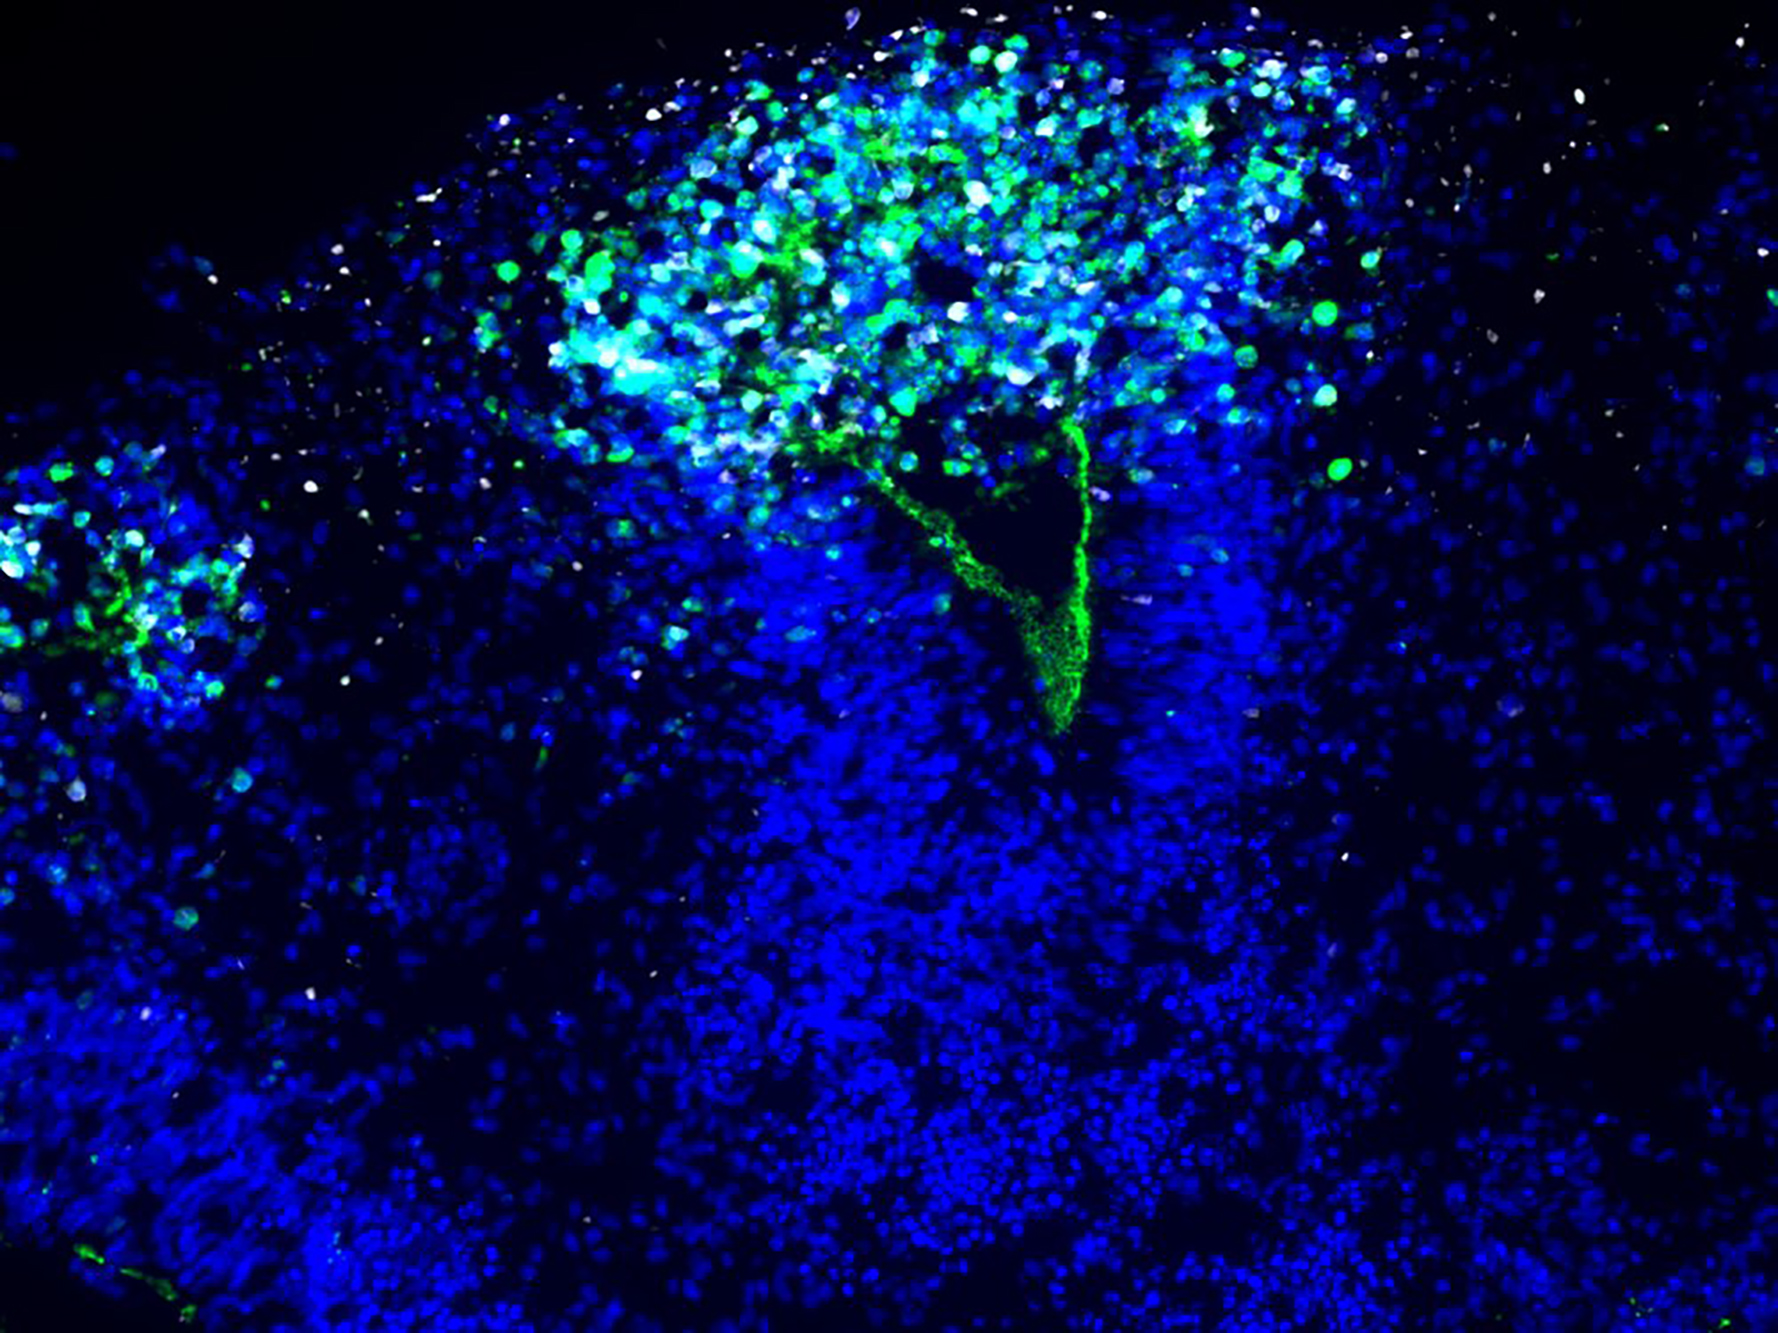

Die Wissenschaftler*innen haben die Organoide zunächst mit HSV-1 infiziert. Während das Virus wütete und die Mini-Hirne zerfielen, färbte das Team Neuronen und Neuroepithel an und machten das Schicksal der Zellen sichtbar. „Da sind wunderschöne Mikroskopie-Bilder entstanden. Sie machen sehr deutlich, was wirklich im Gewebe passiert“, sagt Wyler.

Rybak-Wolf behandelte die Organoide schließlich mit einem antiviralen und einem entzündungshemmenden Mittel, das den TNF-α-Signalweg abschalten konnte. Diese Kombinationstherapie konnte die Mini-Hirne vor Schäden bewahren. „Es gibt also einen Signalweg im Gehirn, der während der Infektion aktiv ist – wenn wir ihn mit den beiden Wirkstoffen abschalten, wird das jeweilige Organoid nicht geschädigt“, sagt sie.